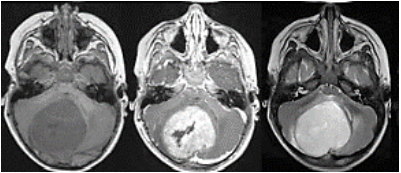

Criança, 18 meses, levada a consulta de rotina na Unidade Básica de Saúde.

Durante a avaliação a mãe relata que a criança estava se desenvolvendo bem, andando, no entanto, há 2 meses parou de andar, está inapetente e por vezes vomita.

Em seu histórico de saúde: nascido a termo, parto vaginal, apgar 9/10, sem intercorrências gestacionais ou periparto. Vacinação adequada para a idade.

Durante o exame físico criança alerta, chorosa, fontanela anterior abaulada, aumento do perímetro cefálico.

Encaminhado a um pronto socorro pediátrico aonde foi submetido a ressonância nuclear magnética (RNM – figura 3):

Figura 3 RNM de crânio

Assinale a alternativa correta a respeito do quadro da paciente.